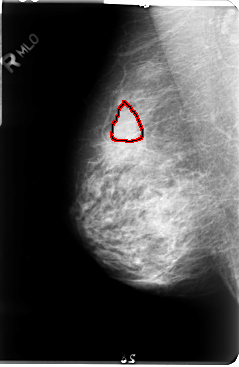

FILE: B_3048_1.RIGHT_MLO.OVERLAY

TOTAL_ABNORMALITIES 1

ABNORMALITY 1

LESION_TYPE MASS SHAPE LOBULATED MARGINS CIRCUMSCRIBED-OBSCURED

ASSESSMENT 3

SUBTLETY 3

PATHOLOGY UNPROVEN

TOTAL_OUTLINES 1

BOUNDARY